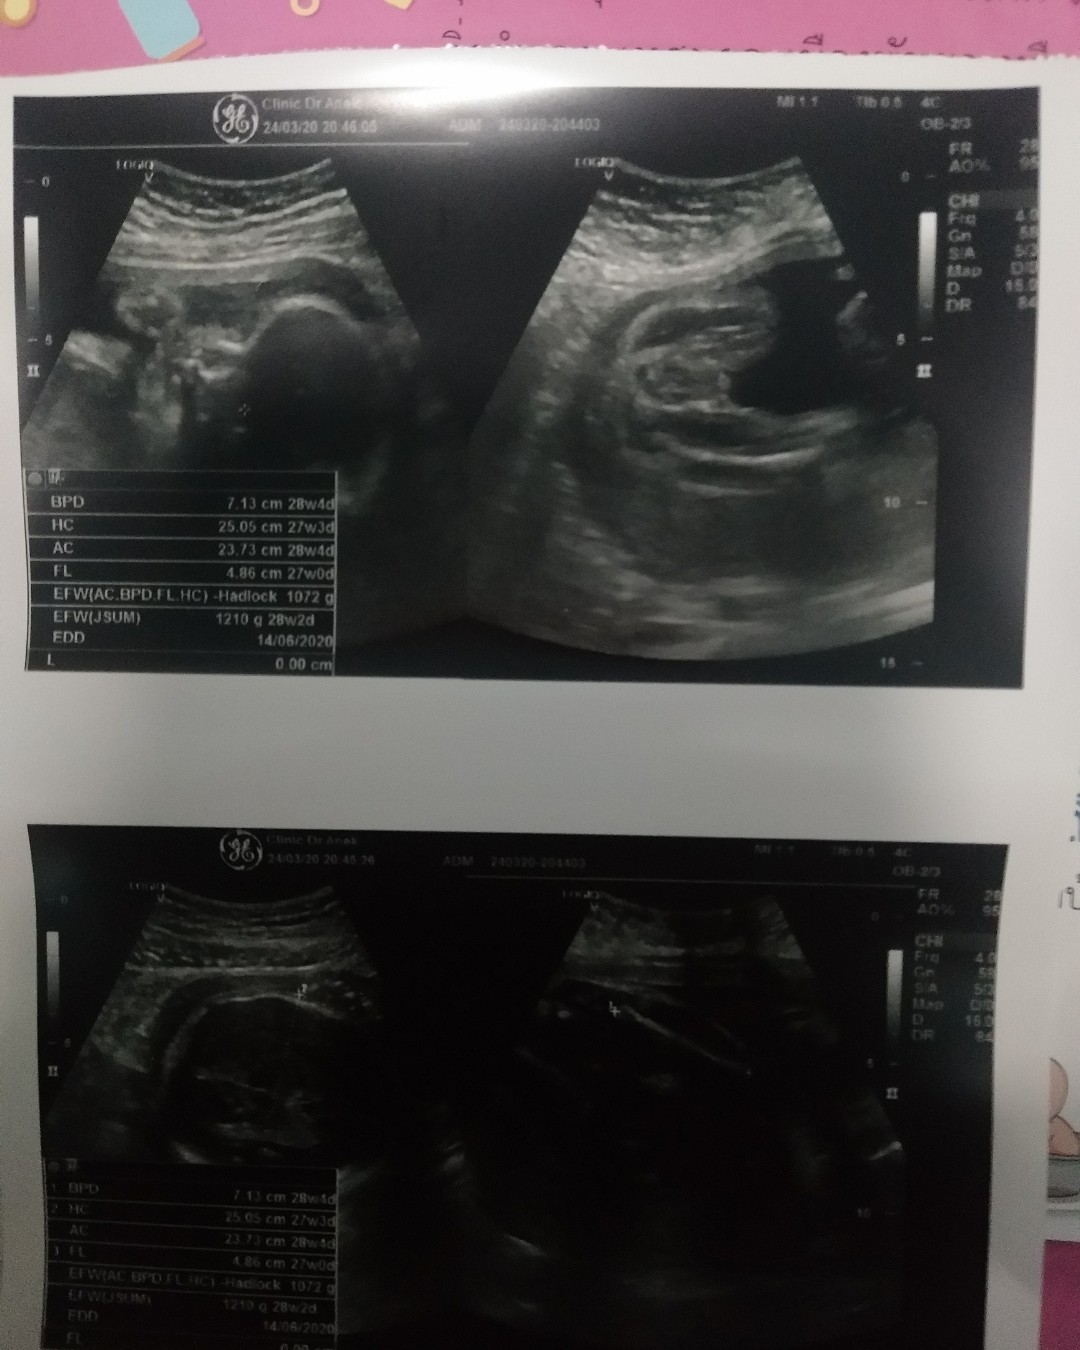

มีคนมาว่าแม่นับวันผิดบ้างหละ คลอดก่อนกำหนดบ้างหละ คือรูปนี้นานแล้ว ตอน16wแล้ว แม่ลงนานแล้วนะค้ะ ตอนนี้ก็ 28wละจ้าา บ้านนี้กำหนดคลอด28มิ.ย.63 เพศชายจ้า?